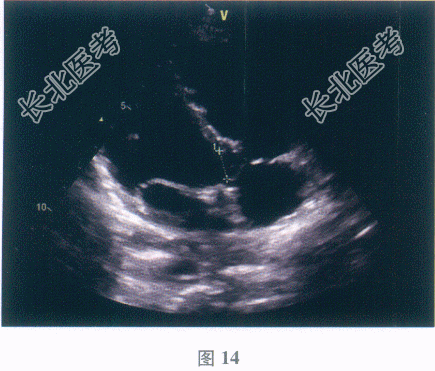

多项选择题3.【提示】血常规回报:外周血白细胞7.8×109/L, 血红蛋白115g/L,血细胞比容23%。尿常规回报: 尿比重1.035,红细胞0~1个/HP, 白细胞0~5个/HP,尿蛋白(-)。心电图检查: 窦性心动过速,左心室肥大。超声心动图检查(见彩图14、15): 室间隔膜部呈瘤样向右室侧膨出,基底宽约12mm, 膨出高度9mm,顶端可见宽约4mm破口, 室水平左向右分流,射血分数(EF)62%。   患者目前的诊断是( )